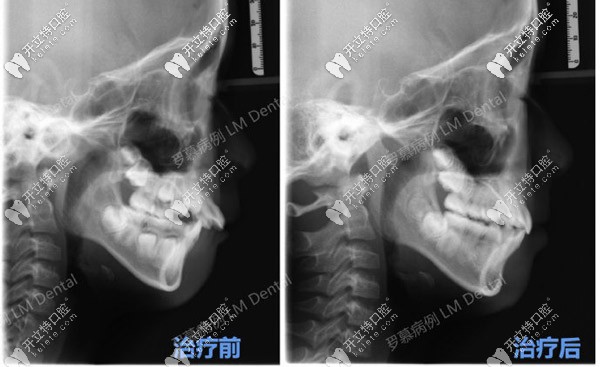

CT可以明顯看到羅慕干預(yù)后的效果

CT可以明顯看到羅慕干預(yù)后的效果▲